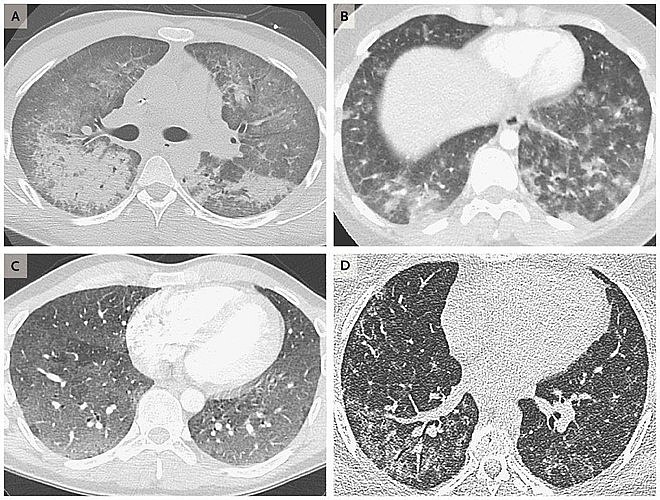

| Hình ảnh scan phổi của 4 bệnh nhân tuổi từ 19 đến 49, cho thấy dấu hiệu tổn thương do sử dụng thuốc lá điện tử - Ảnh : New England Journal of Medicine |